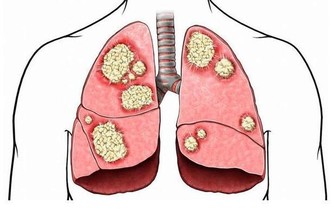

這時,病菌乘虛而入襲擊機體,容易引發各種呼吸系統疾病,導致感冒、氣管炎、關節炎等疾病。